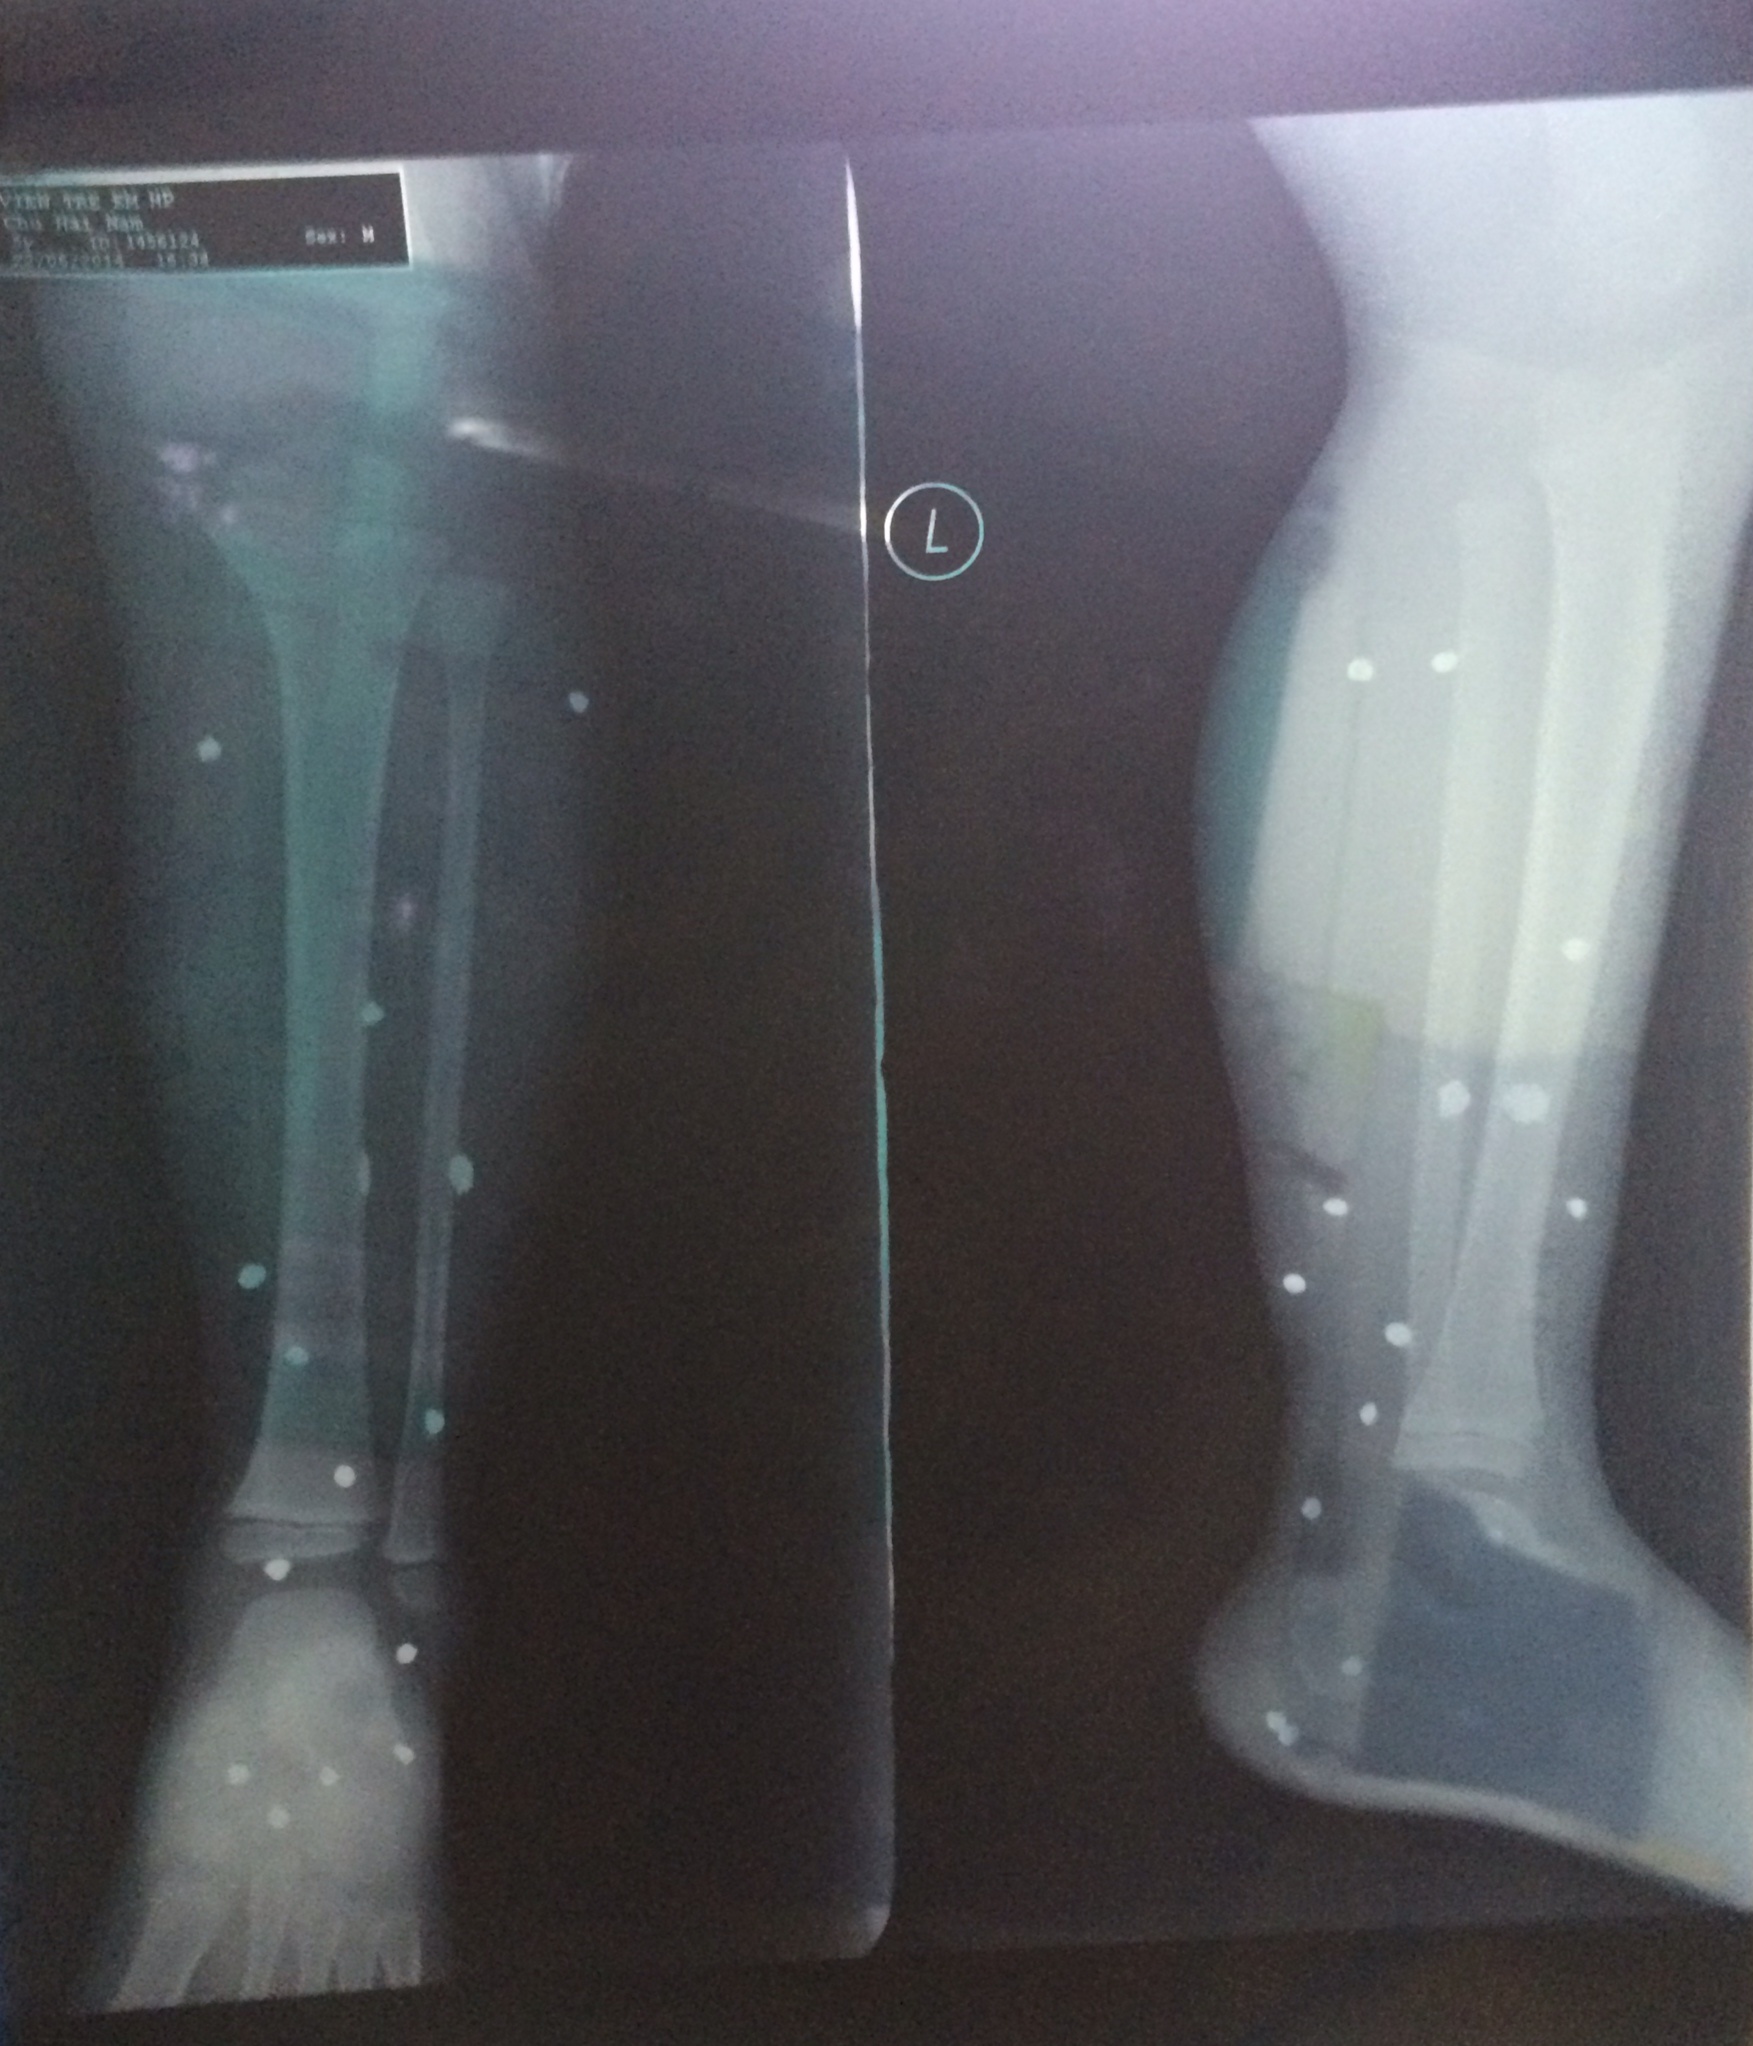

Hình ảnh chụp X-quang các thương tích của bé Nam

Hình ảnh chụp X-quang các thương tích của bé Nam.

Do đứng ở gần cửa, Chu Hải Nam (con trai anh Tấn) bị các mảnh đạn găm la liệt ở chân trái. Cháu bé khóc thét vì sợ hãi và đau đớn.

16h cùng ngày, Nam được đưa đến cấp cứu tại bệnh viện Trẻ em Hải Phòng. Từng cấp cứu nhiều trường hợp bị súng hoa cải bắn, các bác sỹ nơi đây xác định, bé trai bị thương do súng bắn đạn đạn hoa cải.

Do vết thương khá nghiêm trọng nên Nam được chuyển lên viện Nhi trung ương để  điều trị.15 viên đạn (kích thước khoảng 0,5 cm) đã được gắp ra từ chân bé trai 4 tuổi.